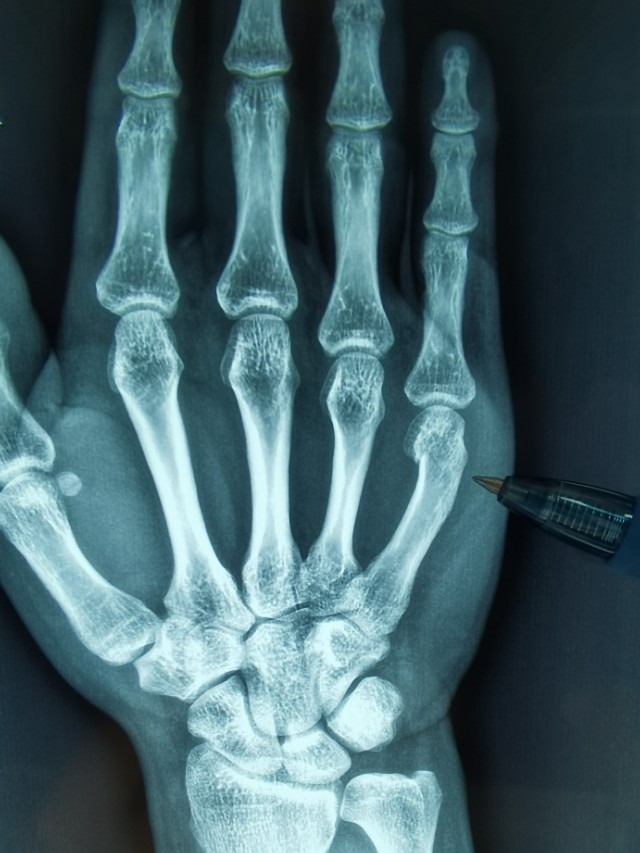

手的第五掌骨颈骨折又称“拳击骨折”,多见于拳头猛然击人、击物、打墙等时损伤。骨折多呈横断或粉碎性,但横断更多见。骨折后由于手部小肌肉的牵拉,掌骨头向掌侧倾斜,骨折向背侧成角。X线片检查可以明确诊断。

固定后常规需拍摄X线片,检查整复位置是否理想,以后每周复诊换药1-2次,一般需限制活动4~6周即可痊愈。